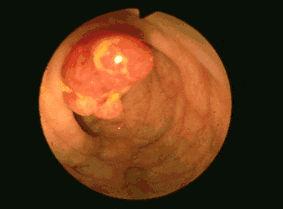

大腸の内視鏡写真  有茎性で頭部は比較的平滑であるが、白苔付着がありびらんないし浅い潰瘍を形成しています。

疾患(病理主体)の分類腫瘍様病変/若年性ポリポーシス

部位(臓器別)大腸/その他

検査方法内視鏡